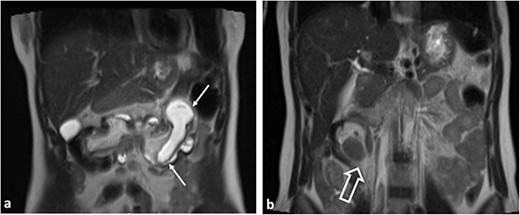

The radiologist’s description of the abdominal MRI with contrast has led to a suspicion of ‘intussusception’ in the transverse colon (Figs 2 and 3).

Coronal T2WI MR images. (a) Tubular lesion (thin arrow) consistent with hyperintense appendiceal mucocele is observed in the left upper quadrant of the abdomen. (b) Ileocolic intussusception is observed in the right lower quadrant of the abdomen (thick arrow).